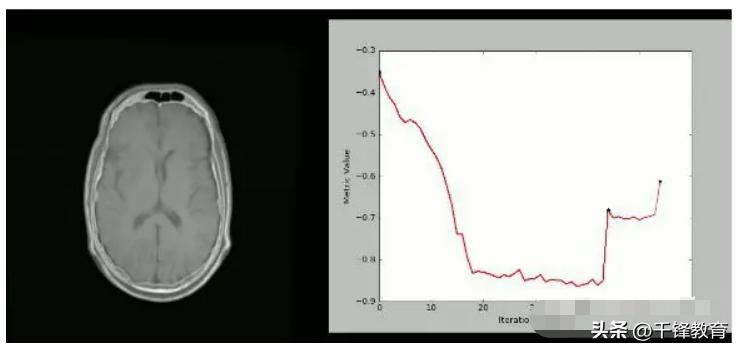

使用SimpleITK和Python创建可视化的严格CT / MR配准过程: